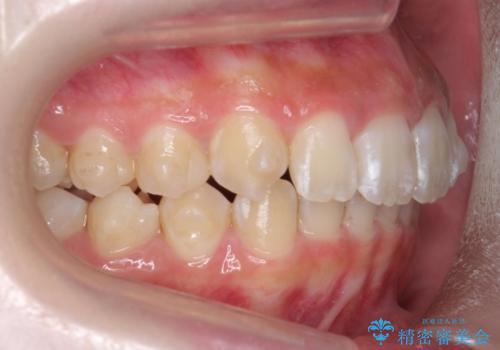

前歯の並び インビザライン 非抜歯で 深いかみ合わせの治療

- 前歯の並びを気にして来院。

上の前歯が内側に倒れこんでいました。

インビザラインで前歯の並びを整えています。

前歯の重なりが大きいいわゆる過蓋咬合を呈していましたが、ある程度適正な重なりにすることができました。